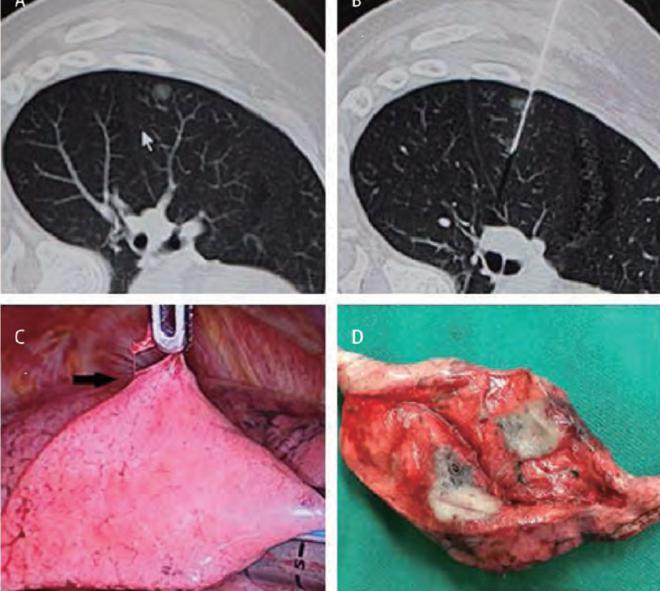

(2.2)“鱼钩”技术(Hook-wire)

CT引导下的穿刺定位技术,又叫Hook-wire技术。手术中使用前端带有倒钩的穿刺针穿过并且锚定病灶,对毛玻璃样结节进行定位。进行胸腔镜手术时,用钳子夹起定位的穿刺针,就能准确地把肺结节所在的局部切下来[1]。(见下图)

真实案例:男性,46岁,因为一个偶然的机会发现了右肺中叶结节。CT显示右肺中叶毛玻璃样影,直径0.6厘米。由于结节非常小,我们建议患者随访观察,但是因为患者平时应酬比较多,抽烟喝酒特别厉害,所以患者的爱人坚持希望手术切除。因为结节非常小,手术当中没有办法摸着,所以采用了Hook-wire肿瘤定位技术,术中冰冻病理检查证实结节是为原位腺癌,因此在胸腔镜下为患者做了右肺中叶切除和淋巴结清扫,术后证实淋巴结没有转移。患者术后不需要放化疗,每3个月定期随访观察就可以了。(下图为病灶在CT上的表现和微创手术切口)